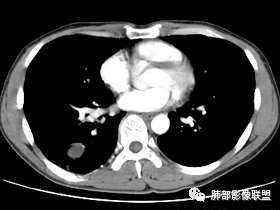

第三,病变旁边胸膜区域有增厚,似乎有些血管增粗,虽然这不是隔离征好发区域;它应该偏内侧一点,但是我们应该最好有重建血管先排除隔离征;从所给图片看,病灶具体走形外面没有看见血管进入,因为是囊性病变嘛。

但是我们先把方向锁定在炎性病变;囊肿伴感染还是结核,这两个在图片上各自特点都有,从目前条件无法完全典型的分辨出来;但是还是倾向于囊肿合并感染。

支气管囊肿伴感染

肺内支气管囊肿并感染一般都是囊腔内的感染,这个病例感染灶延续到远端,还伴有肺气肿;猜测是病变压迫近邻支气管造成的慢性炎症;病变以远的肺气肿,或许是活瓣效应。

肺内型支气管囊肿: 在单个肺段,支气管囊肿与支气管闭锁的鉴别比较困难。支气管囊肿应包括支气管闭锁形成的黏液囊肿,因为他们在病理结构上是一样的。但支气管囊肿多不形成周围的肺气肿。支气管闭锁在病理上也常报告为支气管囊肿:因为标本时常垂直于支气管长轴,造成对闭锁段判断困难,闭锁周围的肺组织多不含炭末。但影像上表现的支气管黏液囊肿和周围肺气肿改变可确定先天性支气管闭锁的诊断。